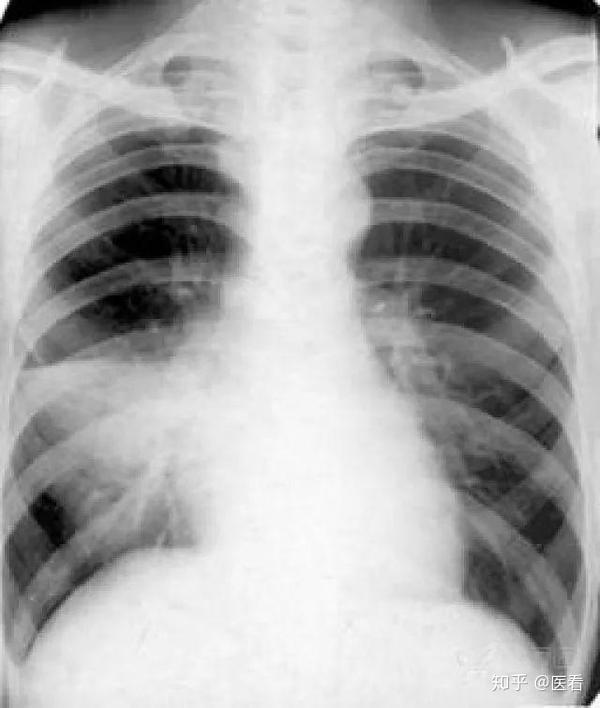

教科书上也很少见这么经典的胸片附肺实变的轮廓征图

胸部x线肺部病变一实变

絮状,模糊,斑片状气腔病变,通常位于中心.01肺泡性肺水肿

肺实变

肺炎胸片

肺实变x线表现图片